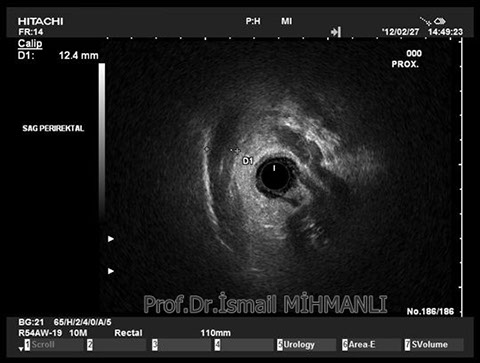

PERİANAL FİSTÜLLER Perianal fistül ve abselerin intersfinkterik anal bez iltihabından kaynaklandığı düşünülmektedir. Crohn hastalarında perianal enflamatuvar hastalık sıktır. İntersfinkterik mesafedeki enfeksiyon yukarıda rektuma, aşağıda cilde, yanlarda dış sfinkteri geçerek iskiyoanal mesafeye uzanabilir. Primer fistülün sfinkterler ile ilişkisini ve abse veya sekonder dal varlığını ameliyat öncesi bilmek, tedavi planı açısından önemlidir. İskiyoanal ve iskiyorektal mesafe tutulmamışsa hastalık daha kolay tedavi edilir. Bu mesafelerde abse veya sekonder bir dal varsa fistül komplekstir ve tedavisi kompleks olmayan fistüle göre değişik olabilir. Bundan dolayı, primer fistül traktı anatomik yerleşimine göre geleneksel olarak sınıflandırılır. Bu sınıflama dörde ayrılır: 1- İntersfinkterik (iç ve dış sfinkter arasında), 2- Transsfinkterik (dış sfinkteri geçerek iskiyoanal veya iskiyorektal mesafeye ulaşmış), 3- Suprasfinkterik (intersfinkterik plandan yukarı doğru uzanan traktüs puborektal kasın Genel Gaz ve Dışkı Kaçırma (Anal İnkontinans) Perianal Fistüller Rektal Tümörler Anal Tümörler Kabızlık Yazılarımız üstündeki bir seviyeden yana kıvrılarak tekrar aşağıya iskiyoanal mesafeye uzanmış), 4- Ekstrasfinkterik (sfinkterlerin dış tarafında rektumdan direkt olarak perianal cilde uzanan traktüs). Endoanal ultrason ile hem primer fistül, hem de varsa sekonder dal ve abse doğru bir şekilde tanınır. Endoanal ultrason ile fistülün anal kanala açılan kısmını (iç uç) görmek kolaydır. Bu hastalarda sfinkter defektlerine de rastlanmaktadır. Sfinkter defekti endoanal ultrason ile kolaylıkla tespit edilir. (bkz. anal inkontinans) Perianal fistül şikayeti olan hastaların az kısmında endoanal ultrason ile bir şey görülemez ise endoanal ultrason probuna ek olarak lineer prob ile anal kanal çevresine bakmak yararlıdır. Çünkü anal kanal bileşenlerinin uzağındaki bir enflamasyon ancak bu problar ile tanınabilir.

Crohn hastasında parİanal enflamatuvar hastalık